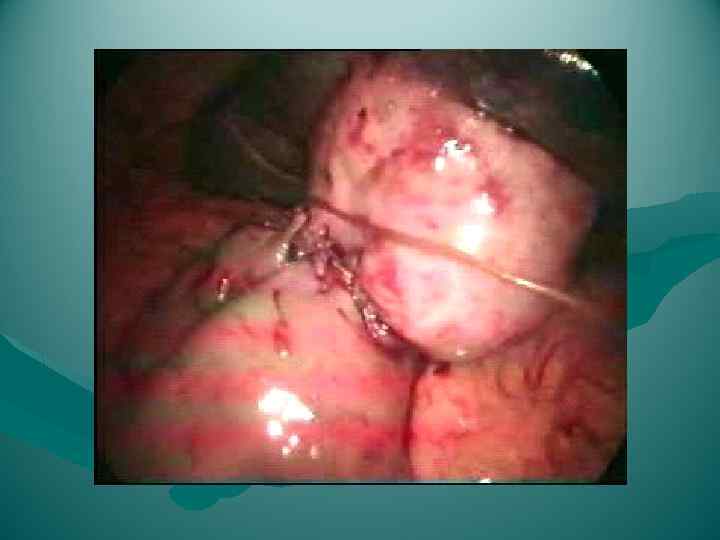

Холецистэктомия от дна

Холецистэктомия от дна

Холецистэктомия от дна

Холецистэктомия от дна

Холецитэктомия от шейки

Холецитэктомия от шейки